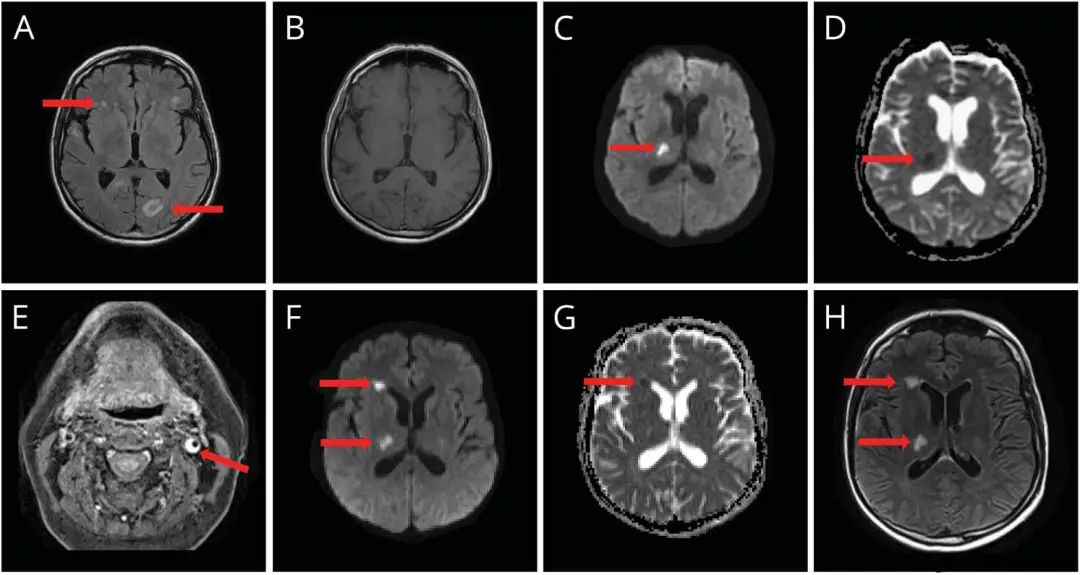

案例配置文件 该患者是一名65岁的农民,他因“不适,头痛,发烧和烦躁不安2周来访问医院”。然后,患者在右侧的第四个颅神经的意识和瘫痪中产生了困惑。腰穿刺被认为是淋巴细胞性脑膜炎。 CSF淋巴细胞为405/μL,单核细胞为90%,蛋白质增加了189 mg/dL(15-45 mg/dl),血清和CSF之间的葡萄糖...